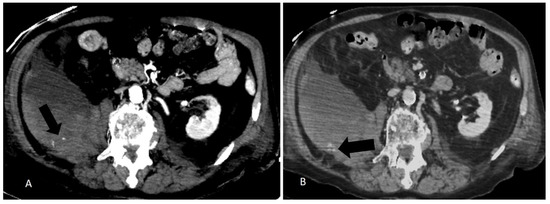

Figure 3.

(A) Arterial phase CT and (B) late phase CT of a right retroperitoneal and ileo-psoas hematoma. Note multiple arterial intralesional blushes (arrow in (A)) show a contrast late enhancement (arrow in (B)).